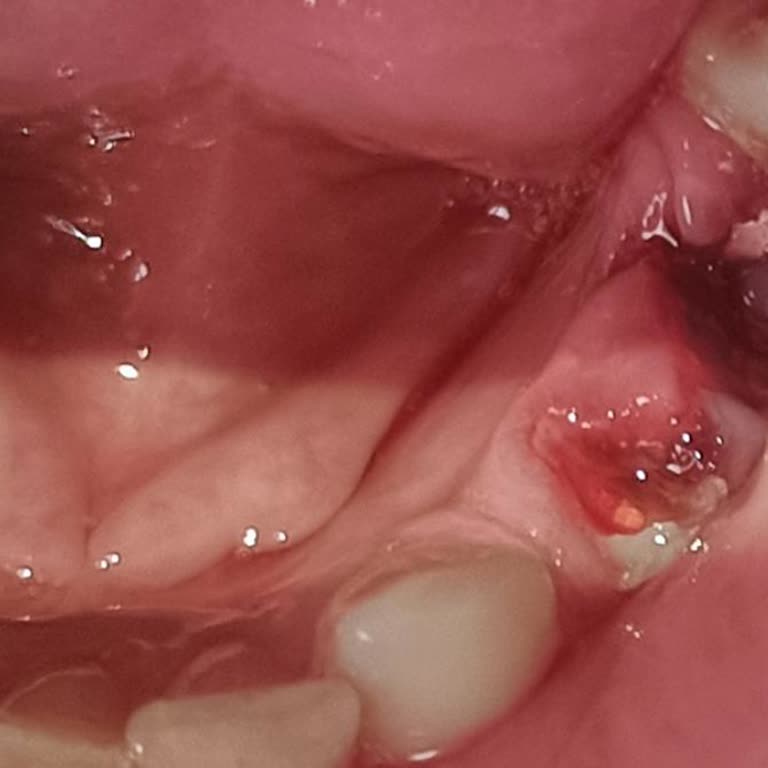

Annem için yazıyorum. Annemin İzmir Gaziemir Semt Diş Polikliniği’nden 17 Şubat sabah saat 09.30’a alınmış bir randevusu vardı. Bu randevu, 14 gün öncesinden kanal tedavisi için planlanmıştı ve annem 14 gündür diş ağrısını antibiyotiklerle bastırmak zorunda kalıyordu. Randevudan bir gün önce polikl...